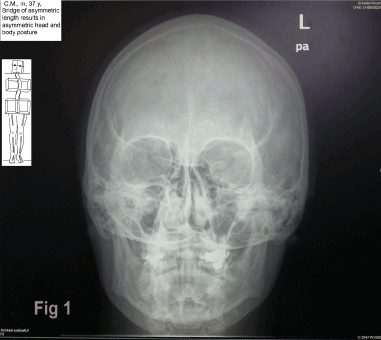

In the x-ray of figure 1, the prosthesis (bridge) in the upper left quarter is lacking about 3mm in length compared with the original teeth length. Consequently, the chewing plane rises up to the left side of the skull, so that the distance between the chewing plane – and the orbita is smaller in the left than in the right hand side. The head shows a permanent lateroflexion to the left and a rotation to the right. This is a function of the postural system to lower the undersurface of the bridge in relation to space and to realign it to the true horizontal. Summing up, the oblique chewing plane seems to be the cause for the lateroflection. Changes in the level of the chewing-plane may be seen frequently in patients with TMD [7-9] and seem to cause “Temporomandibular dysfunction (TMD)”.

Figure 1. X-ray. The skull is positioned in lateroflection to the left and rotation to the right hand side. This hypothetically is caused by a lack in length in the bridge of about 3 mm in the upper left (II) quarter, which makes the chewing plane run more cranial (distance chewing plane - orbital is smaller in the left than in the right hand side). The mandible hangs at an angle to the skull, the left ramus is partially hidden in the skull. The left condyle is shifted dorsal-cranial, the right one ventral-caudal in relation to the fossa.

The x-ray in figure 1 shows the skull in a lateroflection to the left and a rotation to the right. The mandible hangs at an angle to the skull, the left ramus is partially hidden in the skull. The left condyle is shifted dorsal-cranial, the right one ventral-caudal in relation to the fossa (see to the role of condyle positioning [10-13].